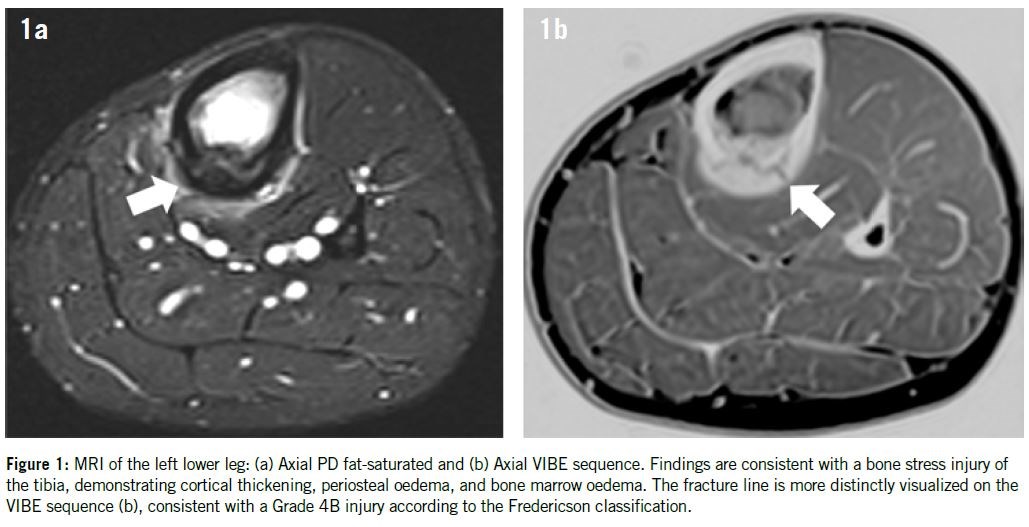

One of the most relevant applications of ZTE and VIBE in sports medicine is the diagnosis and monitoring of BSIs. Once MRI is the modality of choice for BSI evaluation, VIBE sequences can more clearly depict the cortical contour and can reveal subtle cortical disruptions that might be overlooked on conventional MR images. ZTE, with its high cortical bone definition, further refines the assessment by directly visualizing the integrity of the cortex 11. In grade 4b injuries (Figure 1), such as those classified by Fredericson involving the tibia, MRI provides both functional and structural insights. VIBE allows for high-resolution images that show the extent of marrow involvement, while ZTE images reveal whether there is cortical breach, which determines treatment duration and prognosis. In the spine, ZTE and VIBE have been used to confirm complete spondylolysis (Figure 2), providing a radiation-free alternative to CT, especially important in young athletes.

In the Fredericson system, grade 1 represents isolated periosteal edema. Grade 2 includes mild bone marrow edema visible only on T2-weighted images. Grade 3 shows more pronounced marrow edema visible on both T2 and T1-weighted images. Grade 4 represents a linear intracortical fracture. A modification by Kijowski et al. subdivides Grade 4 into 4a: intracortical signal changes without a visible fracture line; and 4b: presence of a visible fracture line18. Although originally developed for the tibia, the Fredericson system is now commonly used for stress injury classification at other anatomical sites as well.